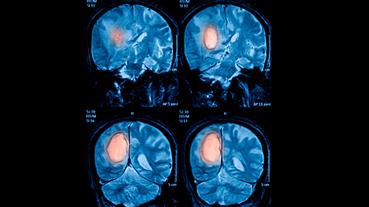

Innovative technologies and alternatives to traditional treatments are transforming the diagnosis and management of neurological conditions. In 2025, NewYork-Presbyterian physicians and surgeons from Columbia and Weill Cornell Medicine used sonication and convection-enhanced delivery to penetrate the blood-brain barrier, validated an adjunctive treatment for subdural hematoma, broadened access to spine surgery, advanced experimental therapies for neurodegenerative diseases, and more. Our specialists have been steadfast in reshaping the fields of neurology and neurosurgery in the pursuit of better patient outcomes and enhanced quality of care.

From cutting-edge research to compassionate patient practice, neurologists and neurosurgeons from Columbia and Weill Cornell Medicine are at the forefront of developing and applying the most advanced approaches to treat debilitating conditions affecting the brain and spine. With a broad range of focus on neurodegenerative and neurovascular disorders to malignant tumors, our innovative and advanced care is leading to new treatment options and enabling patients to achieve the best possible outcomes.